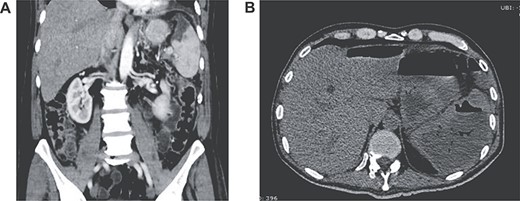

With these findings, surgery was decided. At laparotomy, 1000 cc of purulent fluid was discovered in his abdomen, the upper part of the spleen was filled with necrosis and purulent discharge. After an extensive lavage of the peritoneal cavity, a splenectomy was completed. A drain was left in place and the procedure was completed without complications. He was readmitted to the ICU for postoperative care. Escherichia coli was identified in the peritoneal liquid and after a 10-day scheme of carbapenems, he completely recovered. Pathology reported extensive necrosis of the splenic tissue; spleen abscess was the final diagnosis (Fig. 3A and B). His postoperative course was uneventful, he was discharged after full diet was initiated and the drain was removed because of low and serous output. On follow-ups, the patient is doing well.

(A) Pathology of the spleen with heavy inflammatory infiltrate; (B) pathology of the spleen with necrosis.